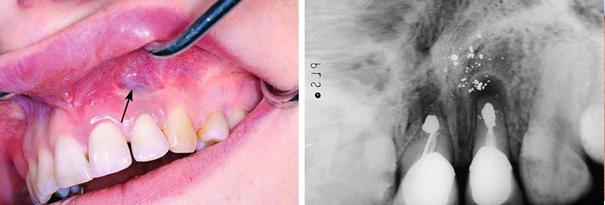

Hình ảnh so sánh một ca cắt chóp trám ngược tốt với chất trám bít kín chóp răng và một trường hợp để rơi chất trám ra mô quanh chóp.

Nhiễm sắc niêm mạc quanh chóp răng tương ứng do rơi vãi almagam ra mô mềm quanh chóp (hình xăm almagam)